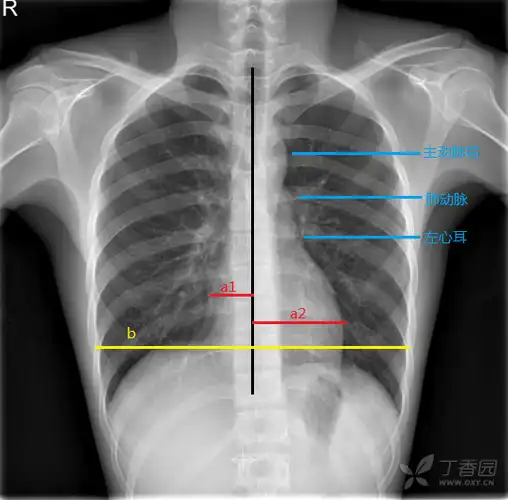

1-1 正常胸部 x 线平片(后前位)